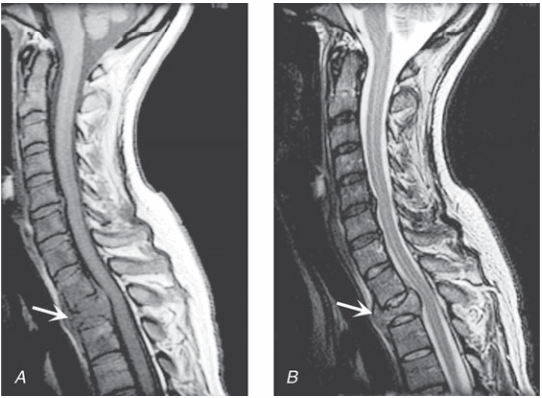

Hình. Chèn ép tuỷ sống ngoài màng cứng do carcinoma vú. Mặt phẳng đứng dọc T1 điều chỉnh A. và T2 điều chỉnh B. MRI ngang qua chỗ nối cổ ngực cho thấy xẹp và thâm nhiễm thân đốt sống ngực thứ hai với sự thay thế và chèn ép phía sau của tuỷ ngực trên. Tín hiệu giảm đậm độ tuỷ xương (A) cho thấy sự thay thế bởi khối u.